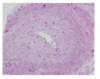

A biopsy - an inflammatory response will be seen

What are the key histological features of T cell-mediated transplant rejection?

Lymphocytic interstitial infiltration

Ruptured tubular basement membrane

Tubulitis (inflammatory cells within tubular epithelium)

Macrophages, recruited by T cells

arteritis

What are the key histological features of antibody-mediated transplant rejection?

- Capillaritis = inflammatory cells in capillaries of the kidney → injury

- also procoagulant tendencies and closure of microcirculation → graft fibrosis

- Immunohistochemistry shows fixation or complement fragments on endothelial cell surfaces